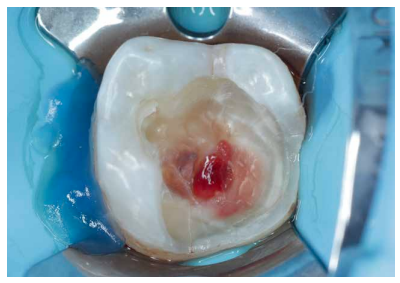

Se continuó con la remoción no selectiva de la caries y de la restauración previa con fresas redondas de turbina y contraángulo (Figura 3). Posteriormente, se expuso la pulpa en la zona más cercana a la lesión en una extensión de unos 2-3 mm con una fresa estéril redonda de diamante montada en turbina con abundante refrigeración. Se observó la pulpa y la sangre era roja brillante (Figura 4). Se controló el sangrado con una bolita de algodón embebida en hipoclorito de sodio 3% que se aplicó durante 2 minutos (Figura 5).

Basándose en los signos y síntomas clínicos no se ha demostrado que se pueda determinar la extensión de la degeneración pulpar. La única manera de saber con determinación esto es la confirmación histológica. Como no se puede realizar una biopsia pulpar en la clínica, durante el tratamiento, el aspecto de la pulpa expuesta tras la remoción no selectiva del tejido cariado, observada con magnificación, y la capacidad de controlar el sangrado serán los factores que marcarán hasta dónde extender la amputación pulpar para llegar a pulpa viable7,8. La presencia de color oscuro o amarillento, ausencia de sangrado o incluso la aparición de pus en la exposición pulpar indica la presencia de necrosis pulpar. En este caso se debe eliminar este tejido hasta identificar pulpa sana y conseguir control de la hemostasia con un algodón embebido en solución desinfectante (hipoclorito de sodio 1-3%)7 .